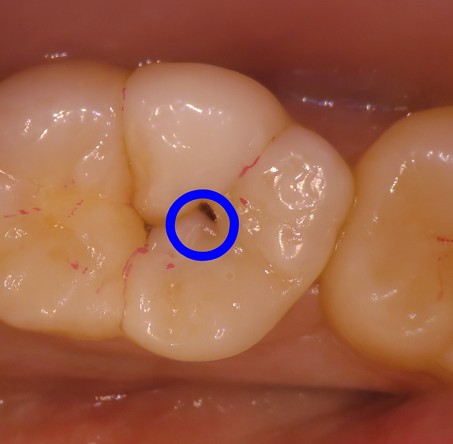

治療前

カウンセリング・診断結果 |

神経近くまで到達する大きい虫歯 |

行ったご提案・治療内容 |

虫歯が大きく、深いところまで削ったため次虫歯になってしまうと神経に虫歯菌が感染し神経を取る治療になる可能性が高いため、歯の寿命を延ばすためにダイレクトボンディングを提案させていただきました。 |